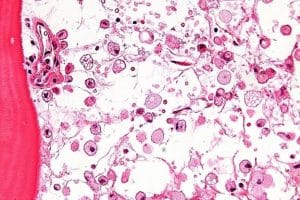

Gaucher disease (GD) is a rare, genetic, autosomal recessive lysosomal storage disorder. The disease is named after the French physician Philippe Gaucher, who originally described it in 1882 [1]. The disease is characterized by the deficiency of the lysosomal enzyme glucocerebrosidase, encoded by the GBA1 gene, located on chromosome 1 (1q21) [2]. Glucocerebrosidase is responsible for hydrolyzing glucosylceramide into ceramide and glucose [3]. The deficiency of glucocerebrosidase leads to the accumulation of glucosylceramide in macrophages, transforming them into Gaucher cells [3]. Gaucher cells infiltrate various organs, primarily the bone marrow, spleen, and liver [3]. These cells have a distinctive appearance, described as “crumpled tissue paper”, with an eccentric nucleus, condensed chromatin, and enlarged cytoplasm [3]. The diagnosis of GD is based on clinical suspicion and confirmed by enzyme activity assays, which measure the activity of glucocerebrosidase in blood samples [3]. The buildup of glucocerebroside initiates a series of eventual consequences, such as inflammation, oxidative stress, and disruption of cellular functions. This contributes to the extensive involvement of multiple systems that are observed in Gaucher’s disease. For example, the invasion of Gaucher cells into the bone marrow hinders the normal production of blood cells, resulting in anemia and thrombocytopenia. The buildup in the bones impairs bone remodeling, which results in pathological fractures, avascular necrosis, and osteopenia [3]. Across all types of Gaucher disease, incidence estimates range from 0.45 to 25.0 per 100,000 live births. The lowest incidence is observed in the Asia-Pacific region. Type-specific prevalence estimates per 100,000 population are as follows: GD1: 0.26–0.63, GD2 and GD3: 0.02–0.08 (limited data from Europe) and Unspecified or overall GD: 0.11–139.0 (highest in North America) [4].

Laboratory investigation revealed a hemoglobin level of 5.5 g/dL, a white blood cell counts of 15900/mL, a platelet counts of 80000/mcL, and a reticulocyte count of 2.3%. Other biochemical parameters, including kidney function, liver function, and serum electrolytes, were within normal range. Abdominal ultrasound showed hepatosplenomegaly. A bone marrow aspiration was performed, which revealed the presence of crinkled paper macrophages in the marrow space as shown in figure 1. A beta-glucosidase test was also recommended, and the levels were found to be 6.2 nmol/h/mg.